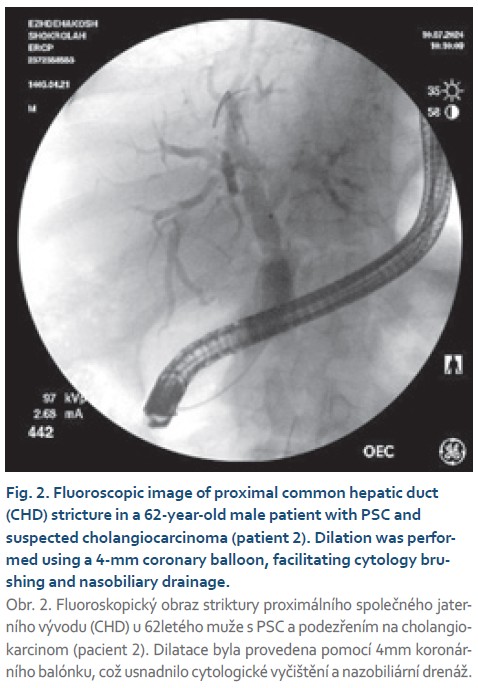

- patient 2: 62-year-old male with PSC and suspected cholangiocarcinoma;

- patient 2: proximal hepatic duct dilation was achieved with a 4- mm coronary balloon, enabling brushing for cytology and nasobiliary drainage;